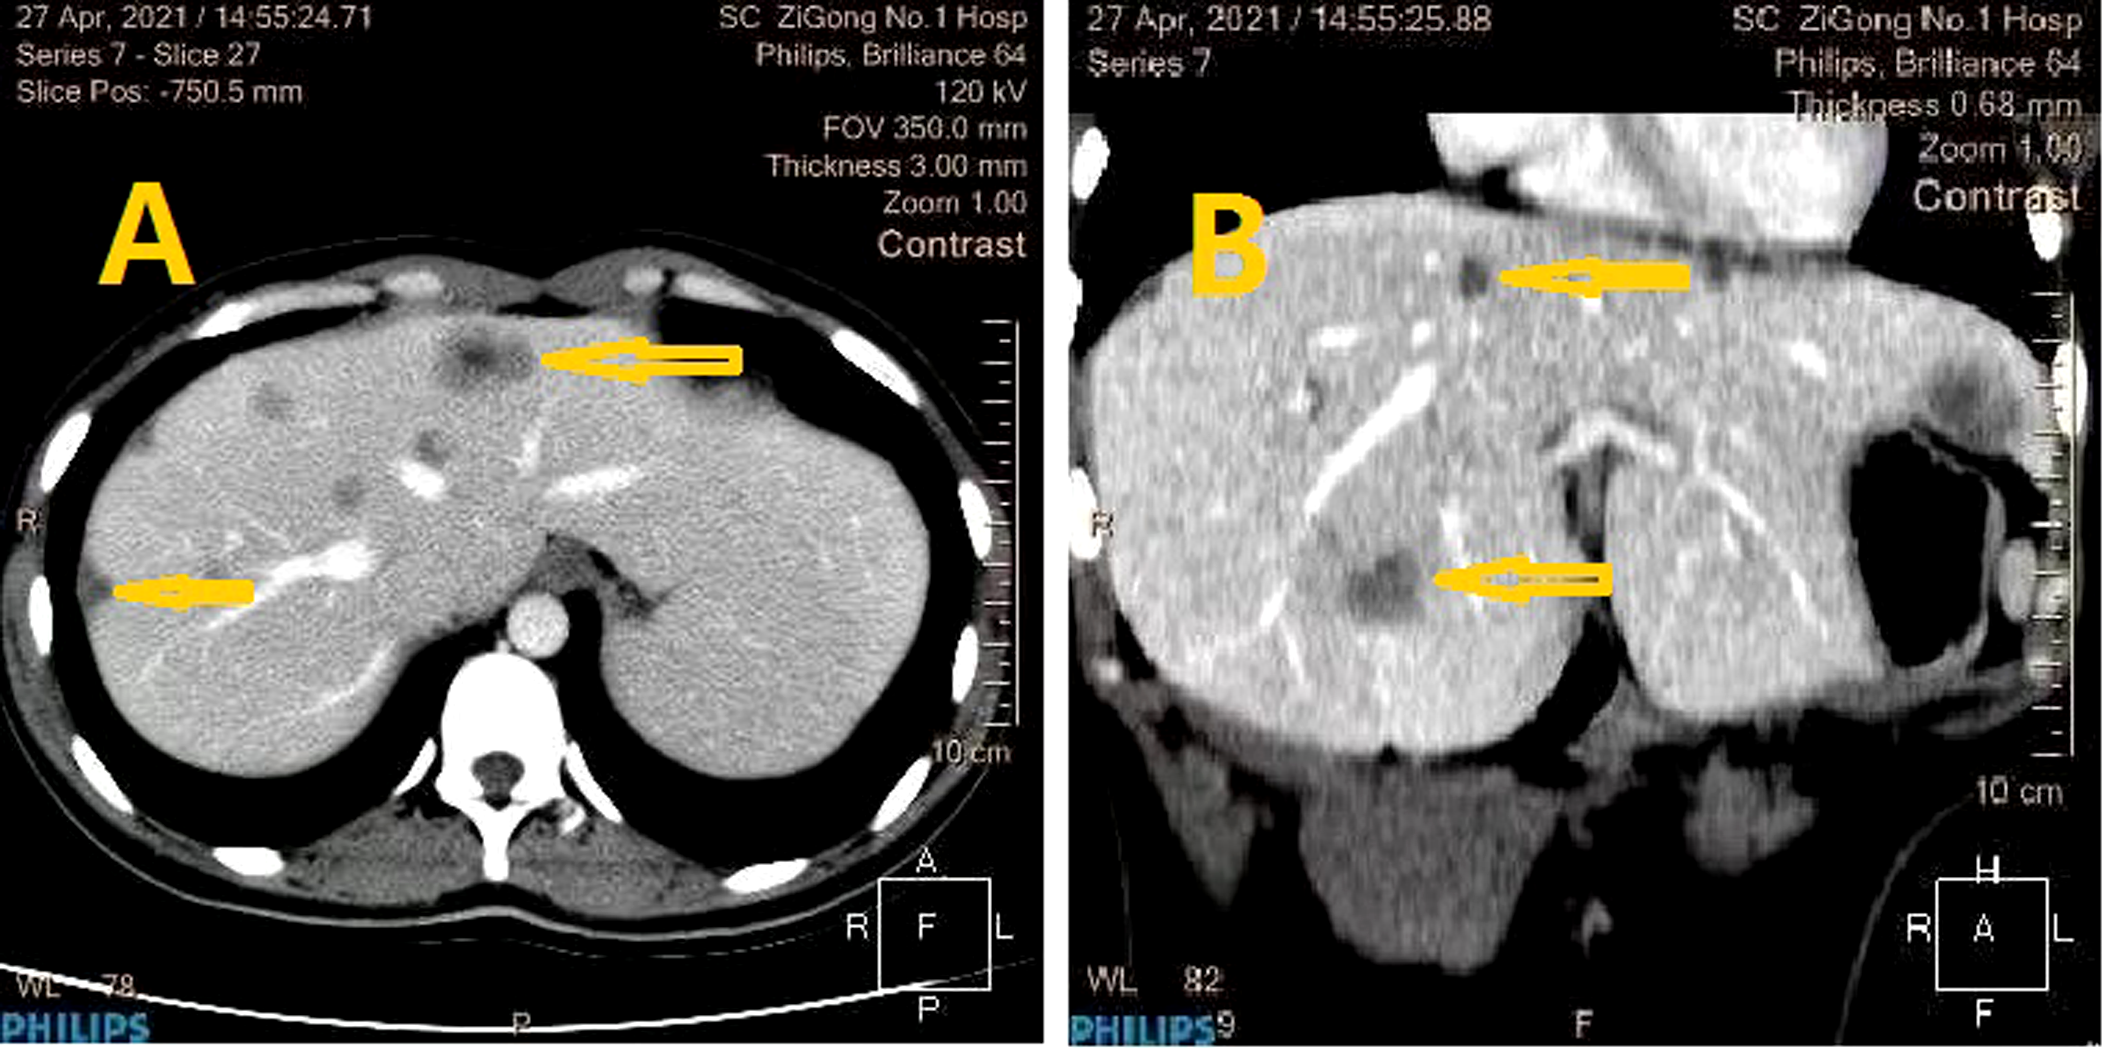

Unfortunately, the patient still had postpartum nausea, vomiting, and abdominal distension and did not defecate for 2 days after delivery. On January 22, all bowel output stopped. Emergency CT indicated a small intestinal obstruction (Figure 1). Gastrointestinal decompression and enema treatment were administered.

Imaging examination: (A) Digital radiology and CT scanning showed gas and fluid accumulation in the small intestine and indicated intestinal obstruction. (B) Liquid, air and high intestinal tension were visible (lesion was marked with yellow arrow).